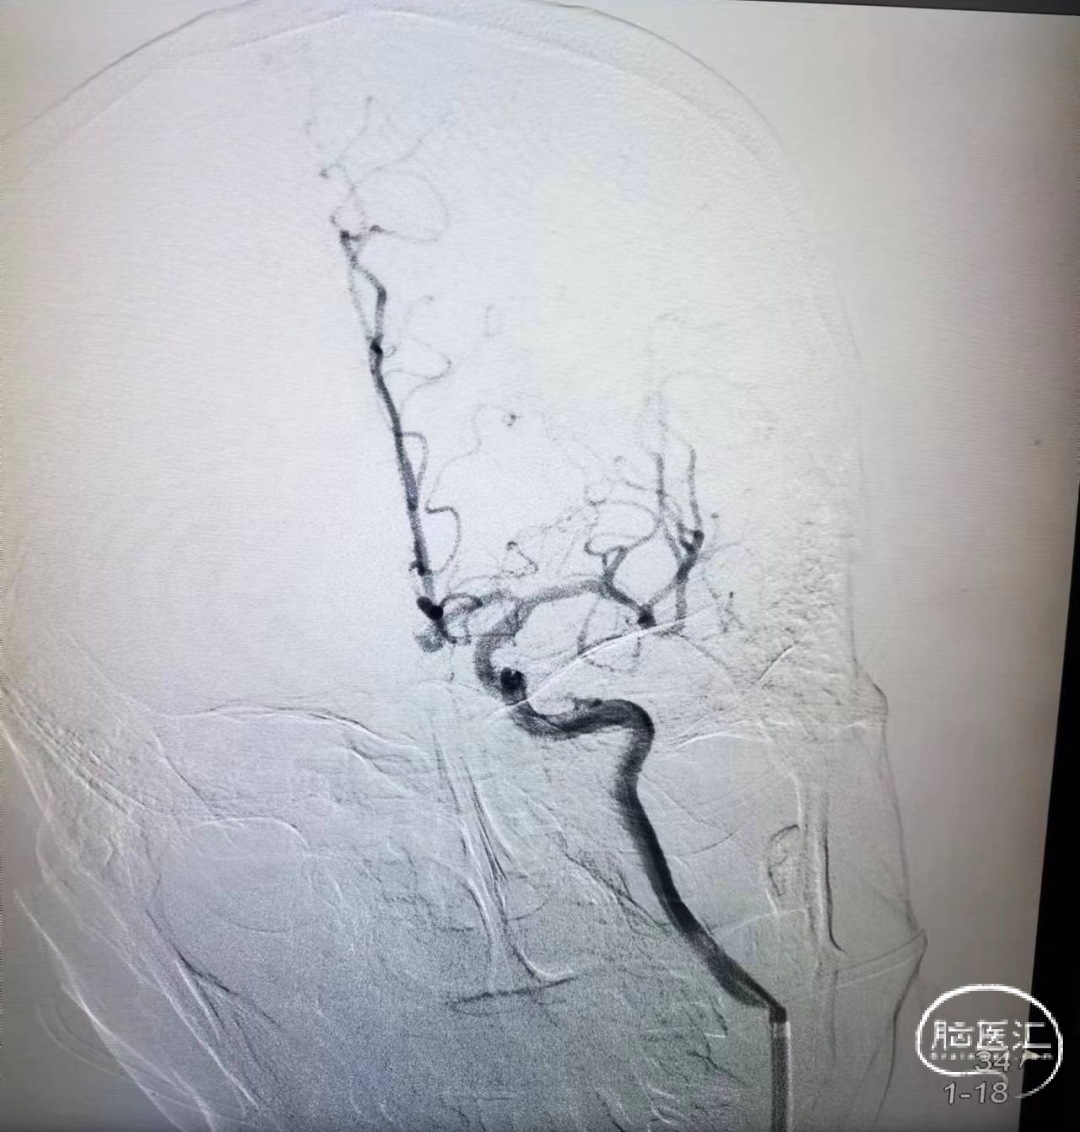

造影证实左侧大脑中动脉M1段闭塞。

策略:BASIS技术。

构建治疗通路,微导管穿过闭塞段后造影确认真腔,置入Syphonet®取栓支架,支架通体显影,提供良好的视觉反馈,全程可视化操作。

首过效应阳性。

沿取栓支架的输送导丝送入SacSpeed®球囊扩张导管,将球囊置于狭窄段充盈球囊进行扩张。

完成扩张后。

球囊泄压后利用Syphonet®取栓支架的锚定效果让中间导管靠近闭塞段;撤出快交球囊后采用SWIM技术取栓;术后造影证实血管再通。

开通后血流再次闭塞,考虑球扩后夹层形成可能;补救性予以电解脱释放Solitarie支架后正侧位造影。